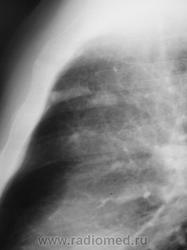

Пациент взят на контроль после проведения профилактической флюорографии.

а в легких изменения?очаговые тени в легких и склеротические изменения тела толкают на мысли о метастатическом поражении.

Сделали "томку".

Мысль всё о метастазах. Клинических проявлений нет никаких? В брюшной полости ничего не растет?

Мы тоже высказали мнение о наличии метастазов. У пациента установлен ( в области) рак предстательной железы, диагноз в ООД вверифицирован.

Я тоже сразу подумала о мтс и это средостение справа как смещено т.е. л.узлы егосместили?